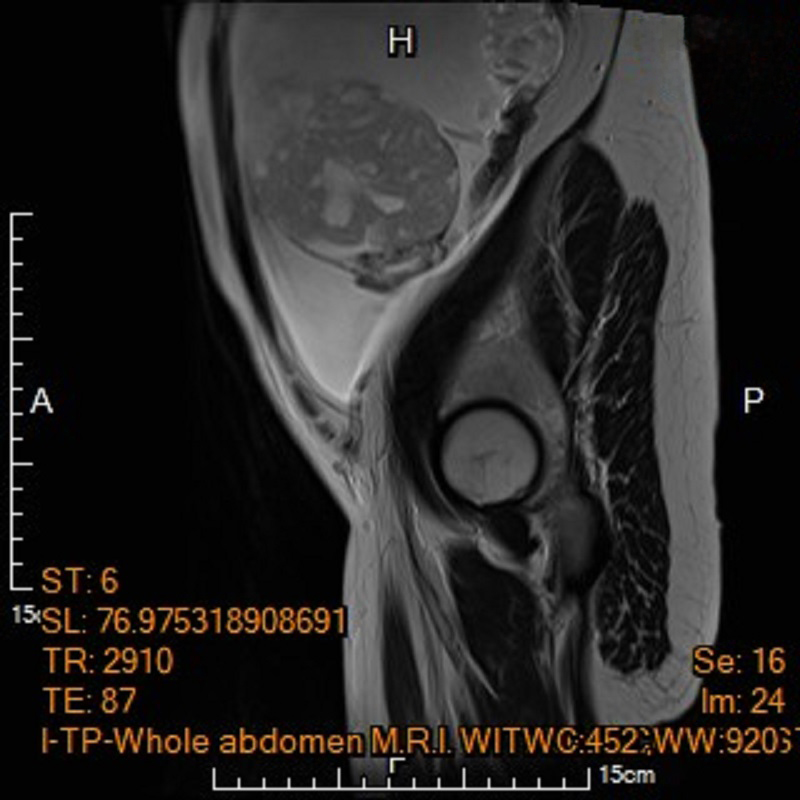

為該名孕婦產檢的馬偕紀念醫院高危險妊娠科資深主治醫師王亮凱表示,李小姐在妊娠20週進行第四次例行性產檢時,腹中胎兒發育情況一切正常,但超音波檢查意外發現孕婦腹腔內積滿大量腹水,及左側下腹部有一個15公分大小、邊界模糊、結構複雜的卵巢腫瘤,孕婦反映有明顯的進食與呼吸困難疑似腸胃道問題,為求謹慎,針對腹水檢體進行細胞檢驗,雖未能於腹水內發現癌細胞,腹部核磁共振影像顯示腫瘤疑似來自左側卵巢,且惡性風險極高,高度懷疑是懷孕中合併卵巢癌。

▲左圖:孕婦電腦斷層呈現腹水與卵巢腫瘤,右圖:電腦斷層顯示子宮內胎兒